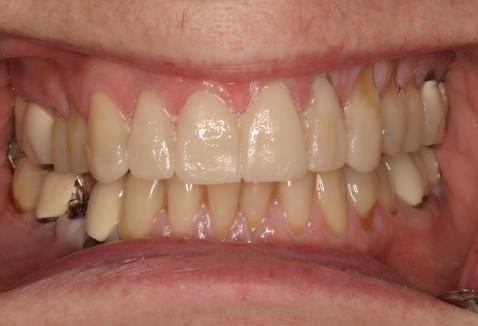

A fost examinată leziunea prezentă la nivelul mucoasei gingivale vestibulare în dreptul premolarului 34 în apropierea joncțiunii muco-gingivale (fig. 1), constatându-se că este vorba despre un nodul fibros gingival care nu necesită nicio atitudine terapeutică (alta decât examinarea periodică) și care nu influențează conduita de tratament local.

CAZ CLINIC

Pacientul EG, 45 ani, fumător, s-a prezentat în clinică pentru rezolvarea multiplelor probleme estetice și funcționale. Planul de tratament general a vizat afectarea parodontală generalizată, îndepărtarea tuturor restaurărilor protetice vechi, extracția dinților compromiși, retratamentele endodontice și reconstituirile de bonturi necesare pentru dinții stâlpi, precum și realizarea unor restaurări protetice înșurubate implantar la nivelul celor 4 cadrane dar și restaurări unidentare la nivelul bonturilor dentare restante.

Figurile 1. Status clinic şi radiologic iniţial; 2. Bontul Balance Base Narrow Straight GH 3.0; 3. Bonturile Balance Base Narrow aplicate imediat post-inserare la 25 Ncm; 4. Aplicarea capelor de protecţie şi sutura; 5. Stâlpii de amprentă înşurubaţi la nivelul bonturilor Balance Base Narrow;